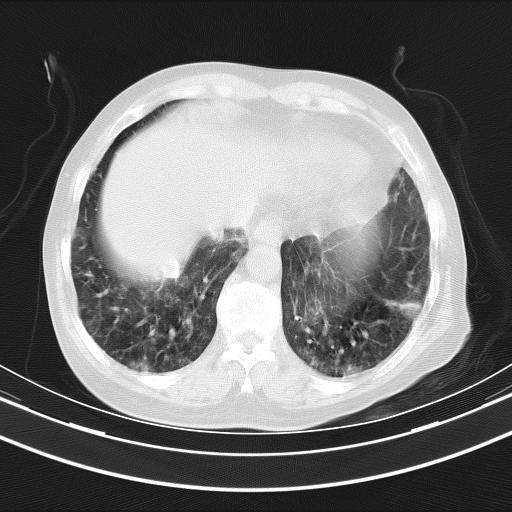

老年女性,嗜睡3天,意识模糊。轻咳,无发热。

两肺慢支炎伴感染,左侧胸腔积液。纵膈及双侧肺门淋巴结肿大建议复查。

双肺多发淡片影,毛玻璃影,,支持支气管肺炎,,建议血气找原因,,嗜睡是否肺性脑病?有没有慢支病史?

双肺炎症,建议抗炎治疗后复查,见过几个老年肺炎病例,没有发烧、咳嗽症状,直接以昏迷就诊。

1)两肺感染性病变;建议抗炎治疗后复查。2)纵隔淋巴结肿大。3)左侧胸腔积液。